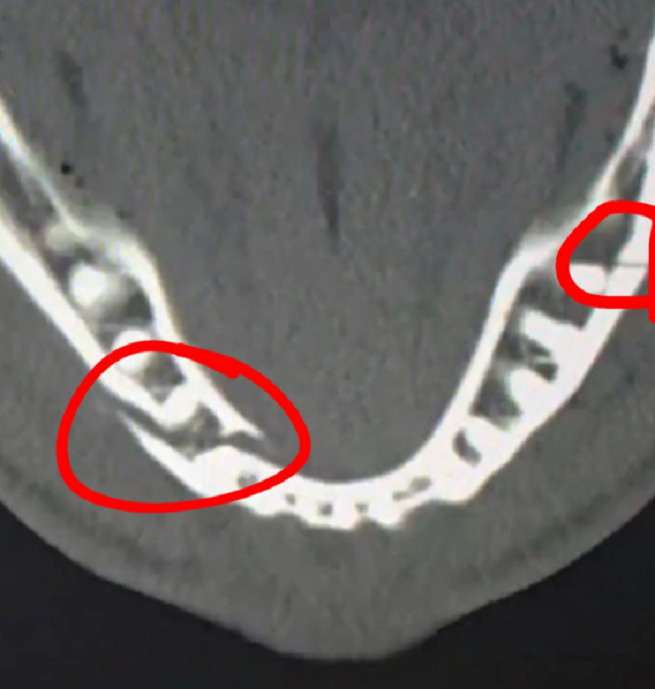

Последствия... После боя с Энтони Джошуа, Джейк Пол госпитализирован с многочисленными травмами. В частности, сильнейшие переломы челюсти в двух местах, существенное сотрясение мозга и многое другое...

Врачам пришлось удалять здоровые зубы, чтобы наложить на переломы титановые пластины! Восстановление для блогера не будет лёгким!